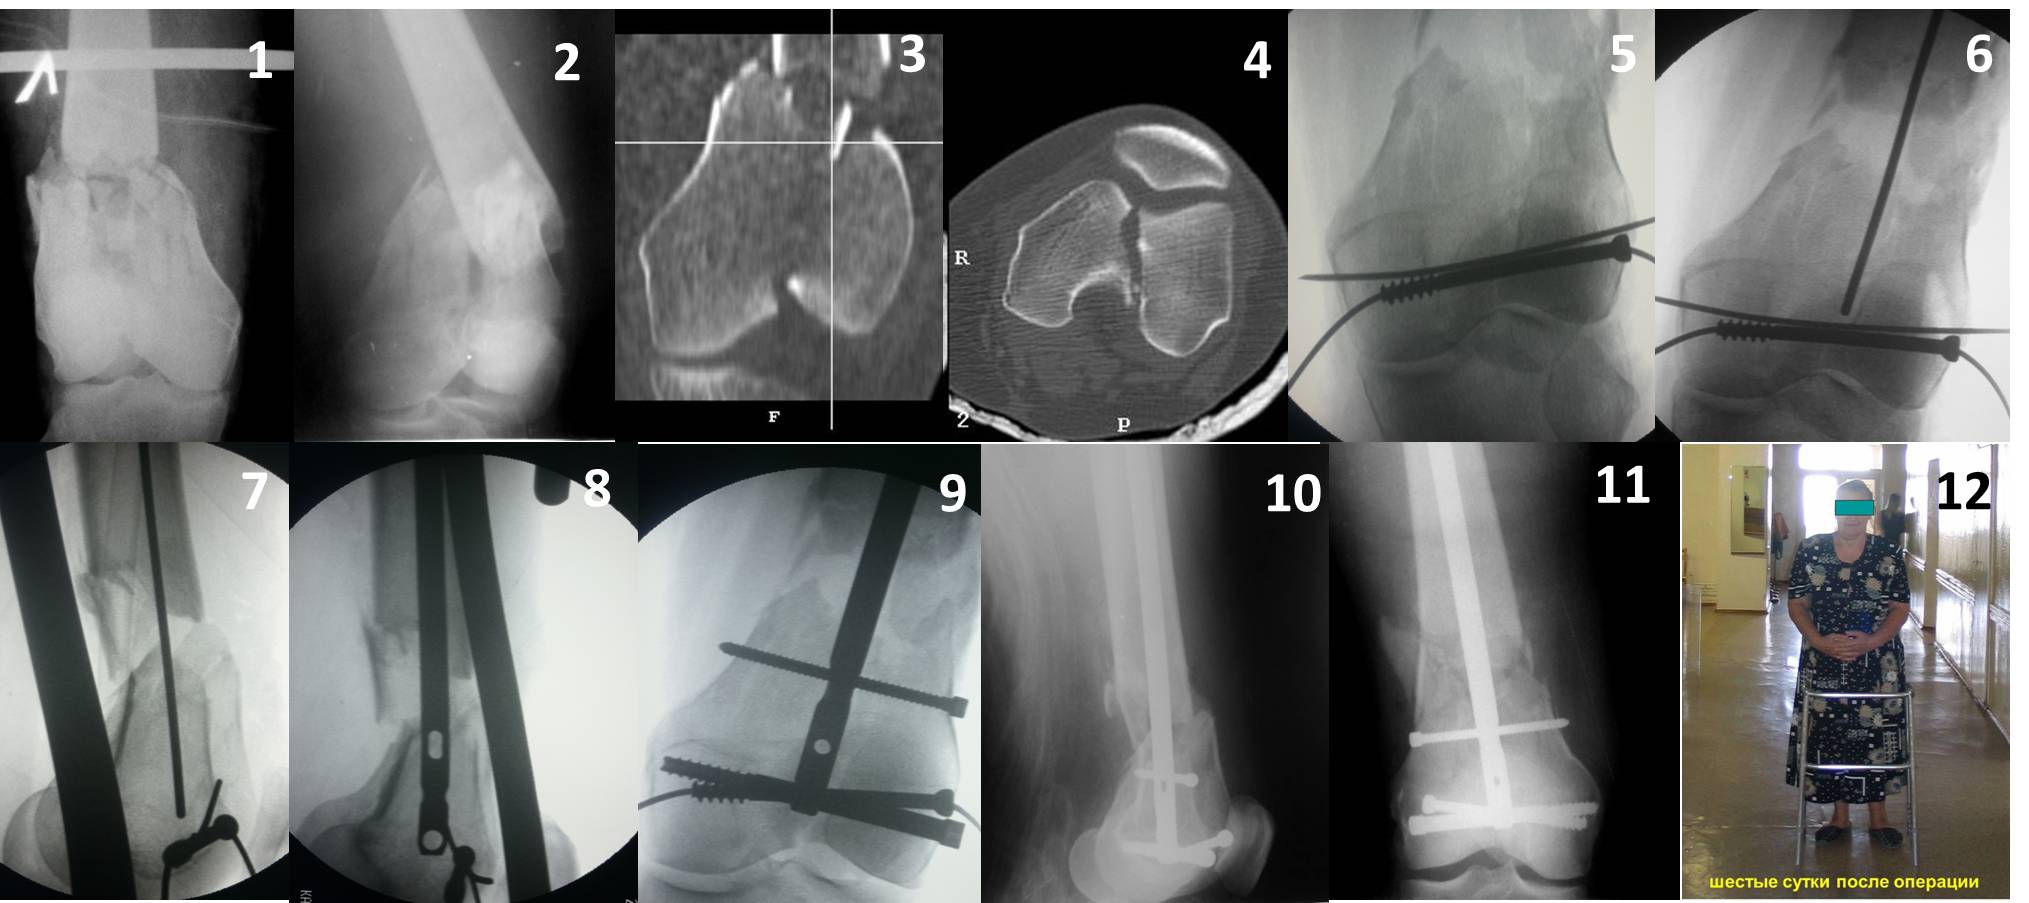

Ответ на эту часть Вашего поста – вложенный файл. Больная оперирована неделю назад по поводу открытого перелома дистального эпиметафиза бедренной кости. После операции она идёт в рентгенкабинет для выполнения послеоперационной контрольной рентгенографии, представленной на слайдах 10 и 11. Узнав, почему её фотографируют, просила передать Вам, Антон, привет.

наружный мыщелок не дорепонироавн - это приводит к вальгусной деформации оси коленного сустава, очень критично для последующей функции.

В приложении пример недавней операции, C3, открытая репозиция, фиксация мыщелков спицами и винтами, ретроградный синтез большеберцовым гвоздем 10,5 мм диаметром, винты 5 мм.

Позволю себе напомнить коллегам ещё раз, что являюсь сторонником антеградного остеосинтеза при переломах дистального эпиметафиза бедренной кости. Такая приверженность основана не на преимуществах внесуставного введения стержня или большем проценте положительных результатов. Она основана на возможности обеспечить блокирование на минимальном расстоянии от суставной поверхности в нескомпрометированной кости и, таким образом стабилизировать максимально низкие переломы. В приведенном Вами случае самый дистальный из блокирующих винтов проведен на расстоянии более 2 см от конца стержня. Из-за того, что к стержню присоединяется кондуктор, на стержне теряется 1-1,5 см его длины, где можно было разместить отверстия для блокирования. И что более важно, вместе с потерянной для этой цели длиной стержня утрачивается для размещения блокировочных винтов, пожалуй, самая ценная часть дистального эпиметафиза бедренной кости. Проблемы дистального блокирования в разных плоскостях, локализации точки ввода стержня при антеградном остеосинтезе – это всё решаемые технические проблемы. Но антеградный остеосинтез низких дистальных переломов бедра при адекватном блокировании в нескомпрометированной кости обеспечивает решение стратегической задачи – стабильный остеосинтез и возможность нагрузки.